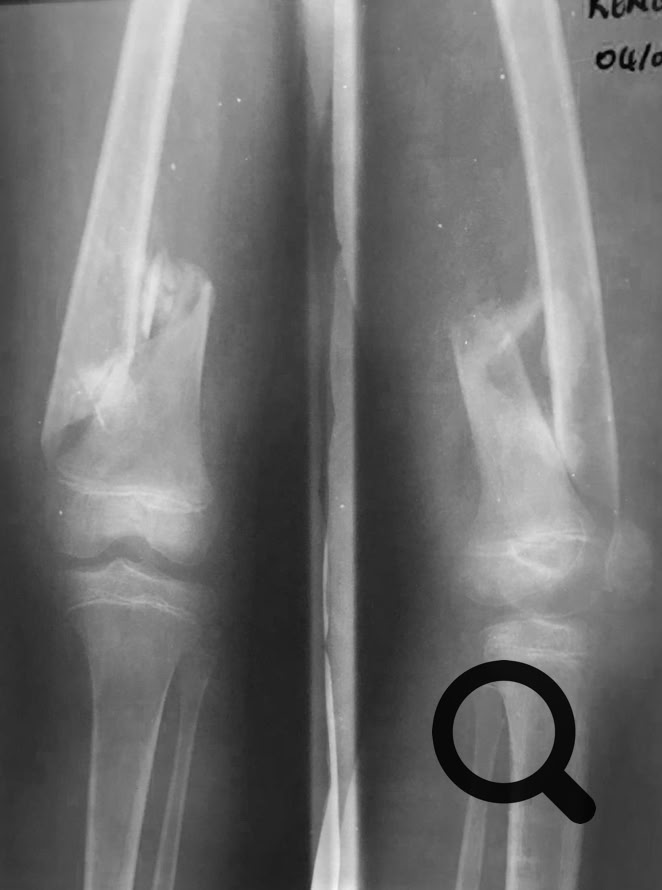

Como no podía ser de otra manera porque nos pasa siempre, nos hemos enfrentado a cirugía de alta complejidad, pseudoartrosis de húmero, fémur y tibia en adultos, así como  fracturas complejas.

Una cosa queda clara, los “masajes tradicionales cameruneses“ no son efectivos en el tratamiento de las fracturas de cualquier hueso, tanto en niños como en adultos y conducen inevitablemente a pseudoartrosis  muy difíciles de tratar.

Y como traca final, el viernes por la tarde cuando íbamos a preparar ya las maletas para el viaje de vuelta, tuvimos  dos urgencias que requerían cirugía  de urgencia. Una artritis séptica de rodilla en un paciente de 21 años operado en otro centro hacía tiempo de un Girldestone por lo que suponemos fueron las complicaciones de una artritis séptica de cadera y con una osteomielitis del fémur. Y un paciente con luxación abierta de rodilla, fractura de cóndilo externo y fracturas abiertas de metatarsianos. Osea, toda la tarde del viernes trabajando.